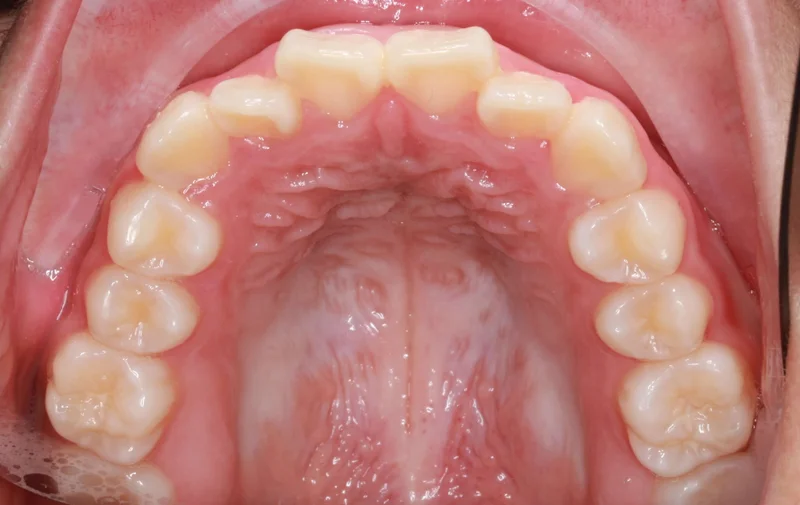

Upper - Before Treatment

Before